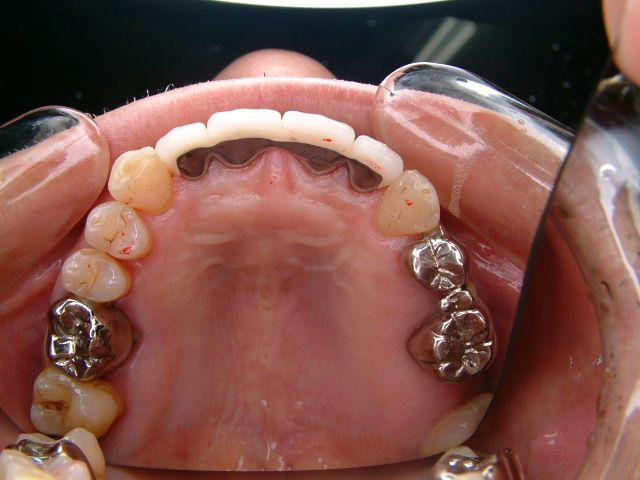

メタルコアー 個歯トレー&各個トレにて印象 |

下顎前歯切端を内側に削って頂いた所 |